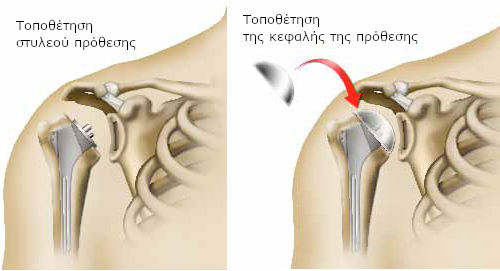

Ο χειρουργός αφαιρεί το ανώτερο τμήμα του οστού του βραχίονα (κεφαλή βραχιονίου) και κόβει το οστό, βάσει υπολογισμών, ανάλογα με το είδος της πρόθεσης που έχει επιλεγεί. Έτσι, προσαρμόζει απόλυτα το οστό στην πρόθεση.

Με ειδικές ράσπες, ανοίγει στη συνέχεια, στο εσωτερικό του βραχιονίου, ένα τούνελ για να τοποθετήσει το πρώτο τμήμα της πρόθεσης (στυλεός πρόθεσης).

Στη συνέχεια, τοποθετεί την τελική πρόθεση και προχωρεί στη στερέωσή της.

Εάν αντικατασταθεί μόνο η κεφαλή του βραχιονίου, μιλάγε για πρόθεση βραχιόνιας κεφαλής. Αποτελείται από το στέλεχος της πρόθεσης (στυλεός), το οποίο εισάγεται στο βραχιόνιο. Στο στέλεχος εφαρμόζει ένα τμήμα, ανάλογης μορφής με την κεφαλή του βραχιονίου (η κεφαλή πρόθεσης).